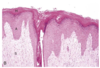

Histological appearance of callus

Epidermal hyperplasia

Histological appearance of acral lick dermatitis

Not really a granuloma!

Epidermal hyperplasia

Granulation tissue

Fibrosis